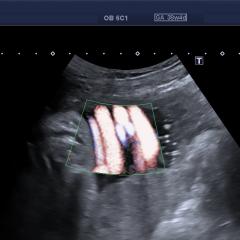

@diagnóstico 96

Se presenta el caso de una paciente de 39 años de edad, primigesta, sin antecedentes personales ni familiares de relevancia. La paciente adjunta el estudio de screening de aneuploidías de la semana 11-14, que arroja bajo riesgo. Las imágenes que… Ver más.